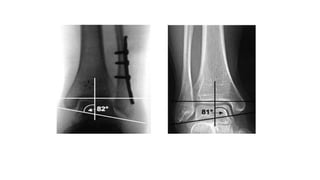

• Radiographic measurements

 Talocrural angle

 measured by bisection of line through tibial anatomical axis and

another line through the tips of the malleoli

 shortening of lateral malleoli fractures can lead to increased

talocrural angle

 Talocrural angle is not 100% reliable for estimating restoration of

fibular length

• Radiographic measurements Talocrural angle  measured by bisection of line through tibial anatomical axis and another line through the tips of the malleoli  shortening of lateral malleoli fractures can lead to increased talocrural angle  Talocrural angle is not 100% reliable for estimating restoration of fibular length